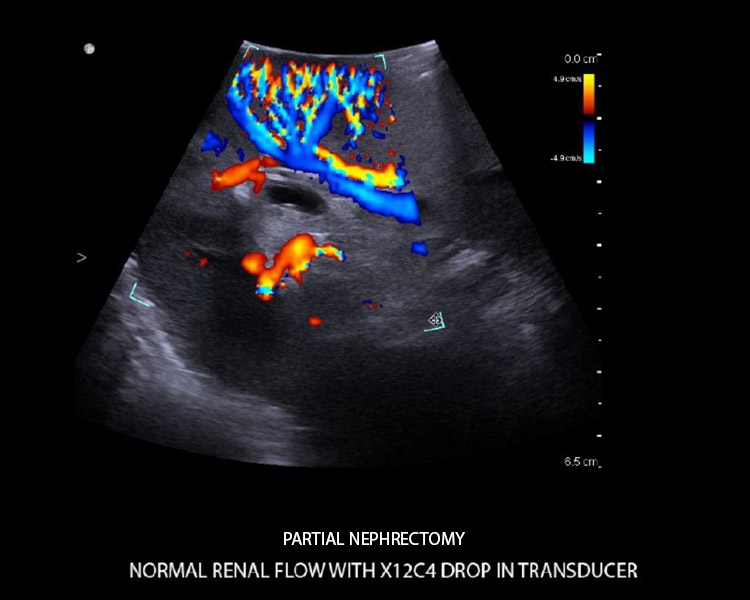

- Hochauflösende Echtzeit-Bildgebung mit herausragenden anatomischen Details.

- Unmittelbare, automatisch optimierte Bildgebung mit No-touch Autogain und Auto Focus – hier sind keine Einstellungen erforderlich.